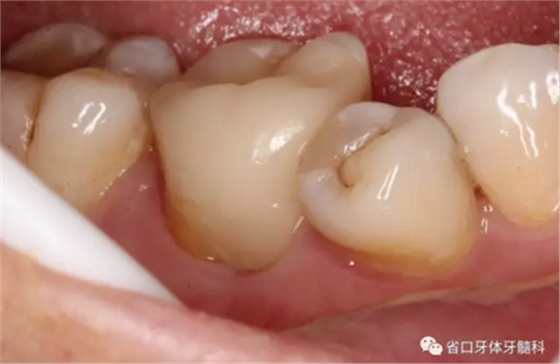

檢查:

46/咬合面見殘留充填物,近中頰尖牙體缺損,缺損周圍見近中頸部繼發(fā)深齲壞,探穿髓,探痛-,叩±,松-,頰側牙齦見瘺口,頰側探及深牙周袋約5毫米。

初步診斷:46/慢性根尖周炎 牙周炎